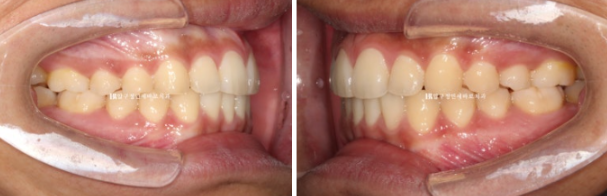

23.12~24.10

배열도 좋습니다.

파란 화살표 반대교합도 해소가 되었습니다